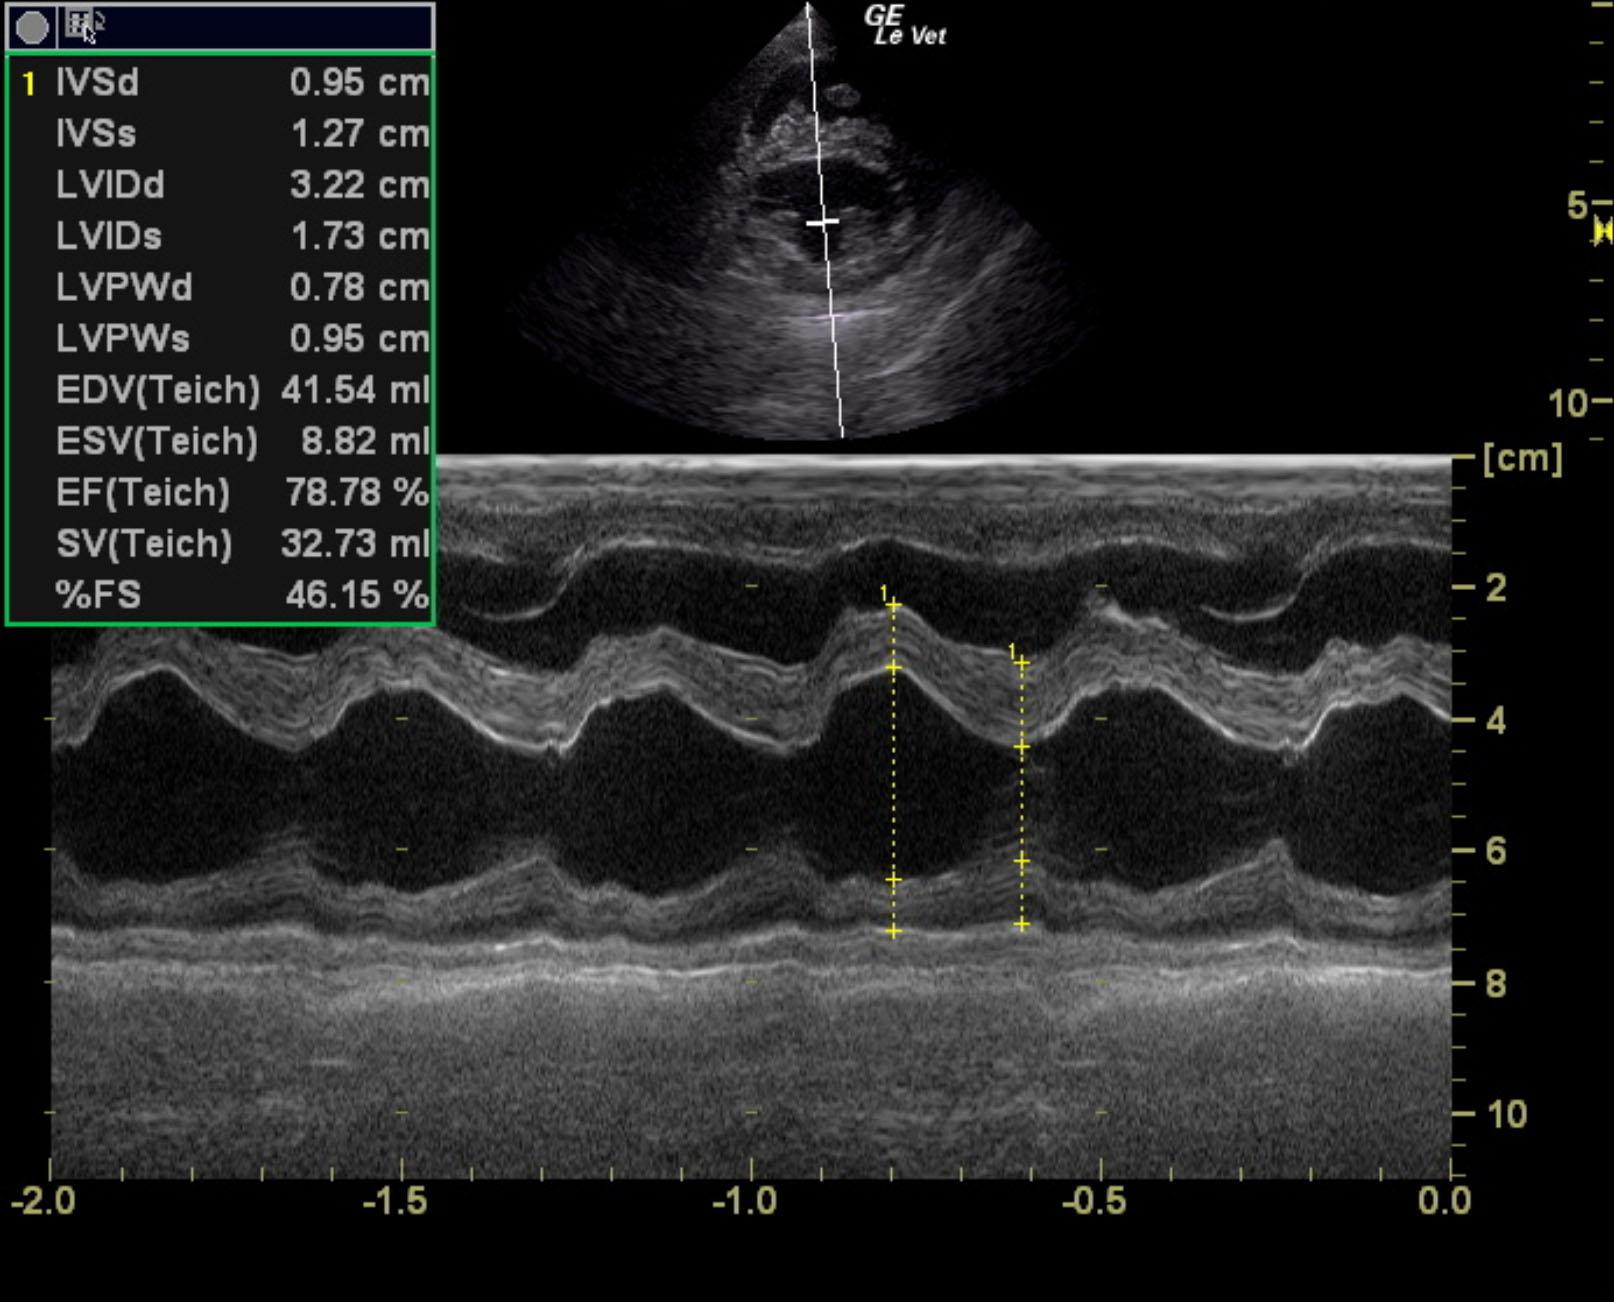

The cardiac presentation revealed moderate left and right sided overload with tricuspid and mitral valve vegetative lesions. Left atrial and right atrial enlargement was noted. Right ventricular overload was noted with flattening of the ventricular septum. Slight prolapse of the anterior mitral valve leaflet was noted. Prolapse of the tricuspid vavle was also noted. Significant pulmonic insufficiency and tricuspid insufficiency was noted. This is consistent with pulmonary hypertension.